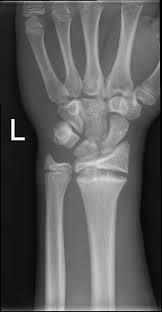

Ulnar variance–what happens with postive and negative?

Positive ulnar variance can cause ulnar impaction syndrome: proximal lunate develops sclerosis, subchondral cysts, and osteophytes

negative ulnar variance: get ulnar impingement syndrome: see edema and degenerative change in ulna/radius.

Can also see lunate osteonecrosis (keinboch malacia..sclerosis + edema in lunate)